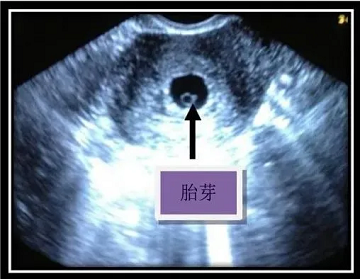

胎芽:胚胎形成的“里程碑”

出现时间

怀孕5周左右,超声下可见宫腔内出现“小芽状”结构(直径约2-3mm);怀孕6-7周时,胎芽长度可达10mm以上,形态更清晰。